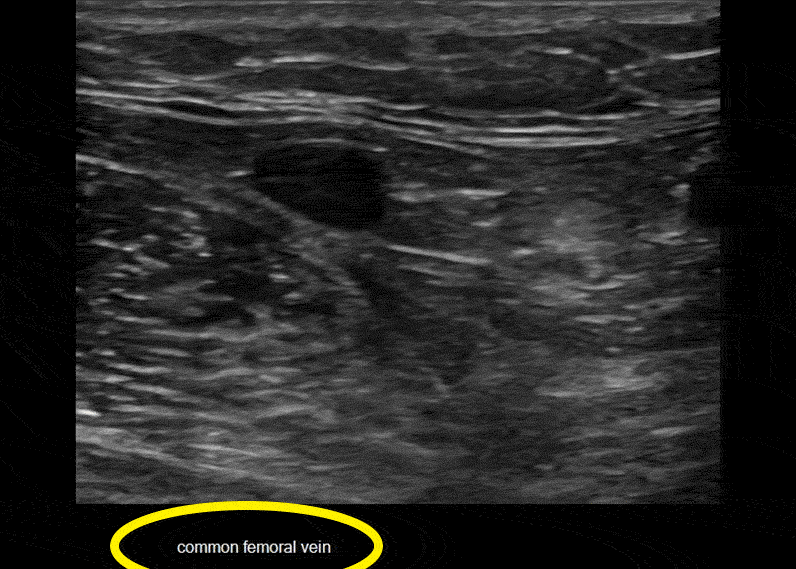

A mistake novices make is finding an impressive looking vein and mistakenly think that it is a deep vein – usually the common femoral vein or the femoral vein. Remember, a deep vein will always have an accompanying artery. They never run by themselves. If you are seeing an isolated vein, it’s not a “deep vein” and in this case is likely the saphenous vein. This happens in the popliteal fossa as well.

In the clip above, we actually catch a glimpse of the femoral vein in the right lower part of the image during the compression. Learners make this mistake frequently. Finding the SFJ is an orienting landmark you should use to begin your study. That’s home. Start from home every time. If you are finding veins without accompanying arteries, you probably need to increase the depth setting or at least scrutinize the deeper part of the image.